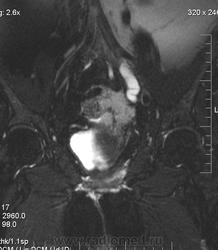

очень характерная картина для метастаза рака яичника, к сожалению.

Не могу достоверно определить локализацию метастаза брюшной полости, вероятно в лимф. узел с инвазией оободочной кишки. Рецидив С-r левого яичника думаю, что с инфильтацией левой стенки прямой кишки и культи влагалища, вторичная лимфаденопатия л/у малого таза. каликопиелоуретероэктазия (инвазия нижних отделов левого мочеточника?) Холедох широковат, но желтухи по внешнему виду нет.

Прорастание левого мочеточника рецидивной опухолью есть 100%, метастаз в большой сальник характерен для рака яичников, как и сигнальные характеристики его. Культя в данном случае шейки матки.